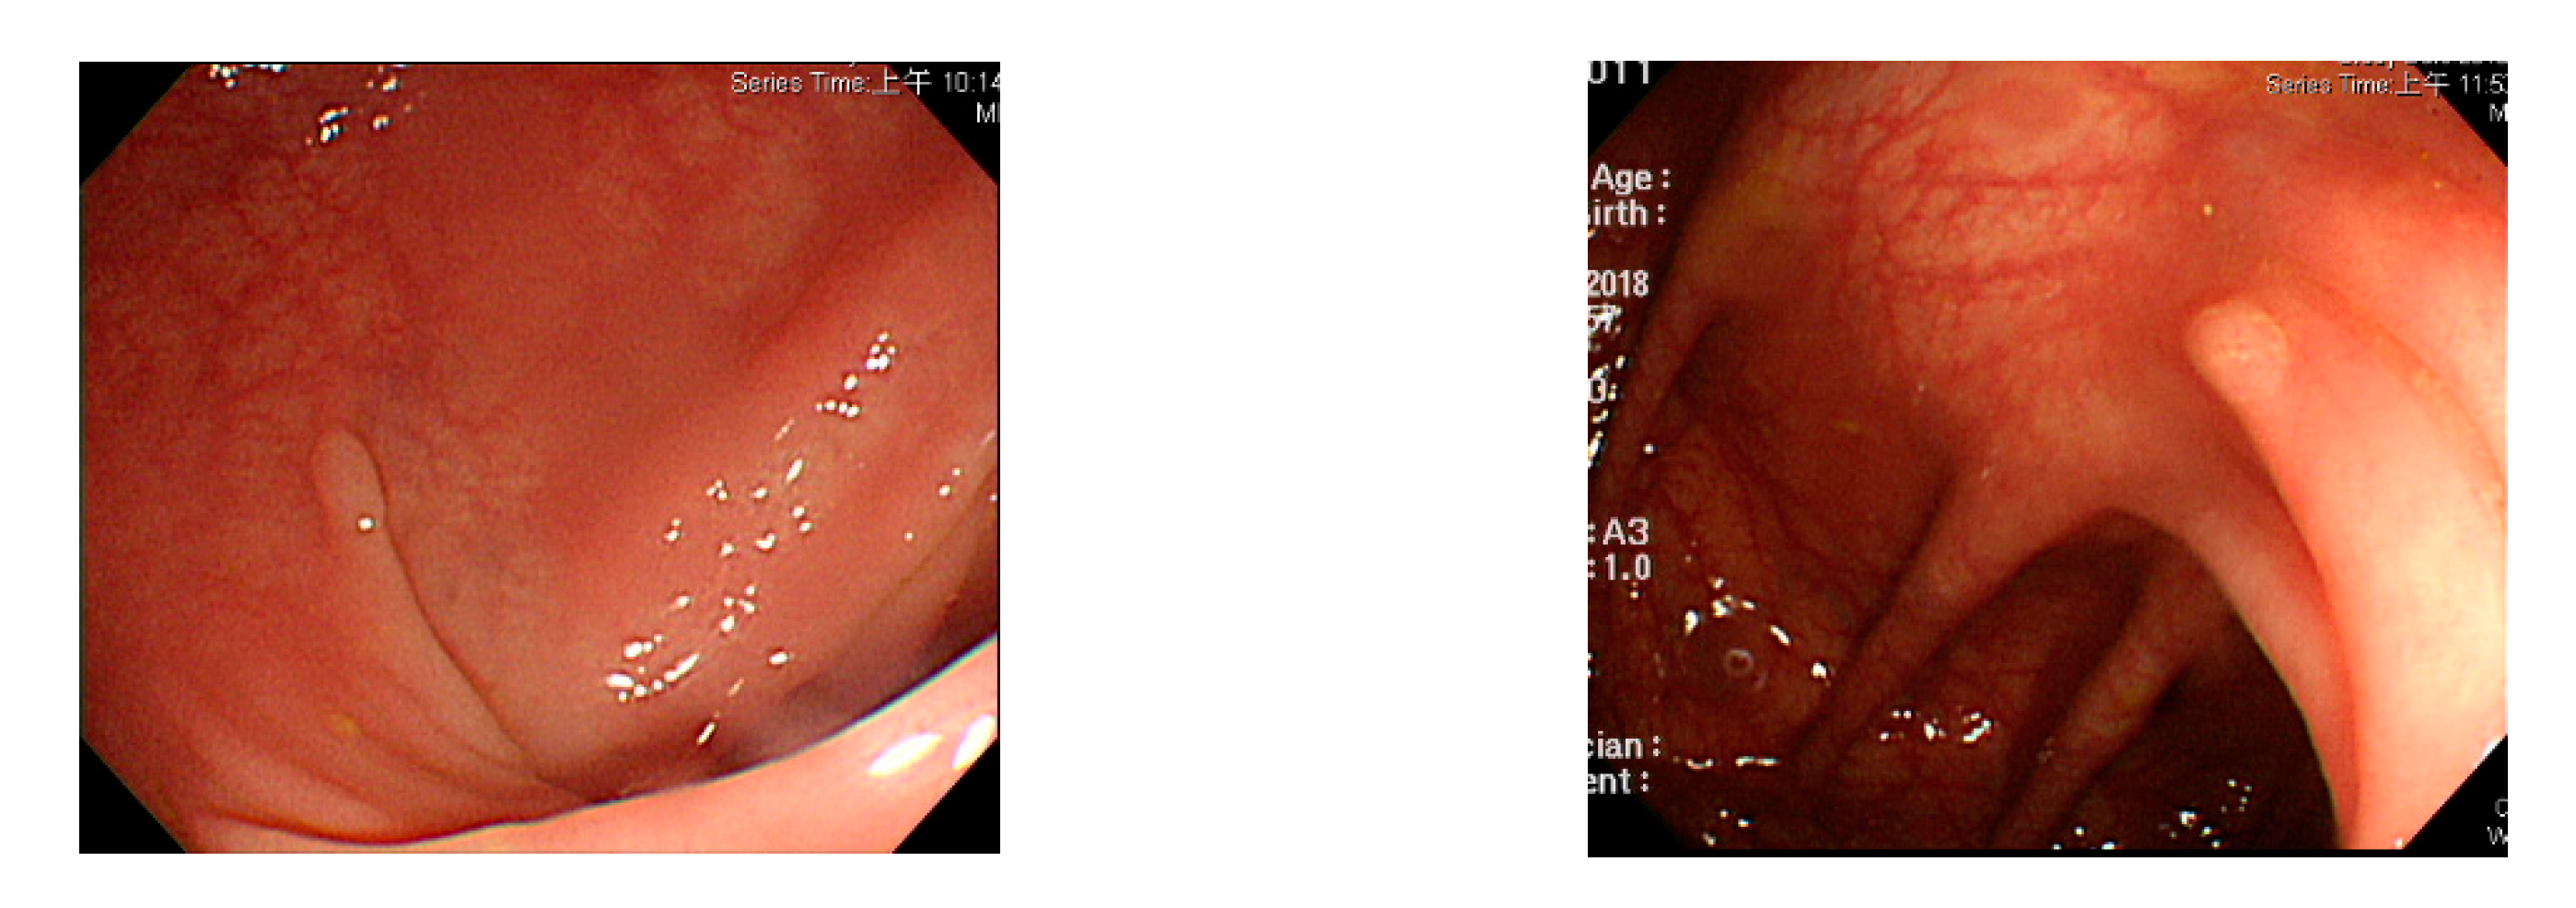

Figure 3.

Small texture of polyp and intestinal wall.

Currently, many medical images are processed into grayscale images, such as ultrasound, computed tomography (CT), and magnetic resonance (MR) images. Tan et al. [44] applied a gray-level cooccurrence matrix and CNN to CT images for polyp diagnosis. Zhang et al. [45] compress the three-channel color images of chest CT to grayscale images. A five-layer deep CNN with stochastic pooling is used to diagnose chest-based COVID-19. Xie et al. [46] mentioned that in deep learning, colors are not the key features influencing accurate image classification. They also discovered that in X-ray image classification, the speed and accuracy of processing grayscale images were considerably higher than those of processing RGB images. The grayscale method used was ITU-R Recommendation BT.601 [47]. Moreover, misjudgments were easily made in the presence of excessive intestinal wall textures, when polyps were too small (Figure 2), and when polyp textures were similar (Figure 3) to intestinal wall textures.